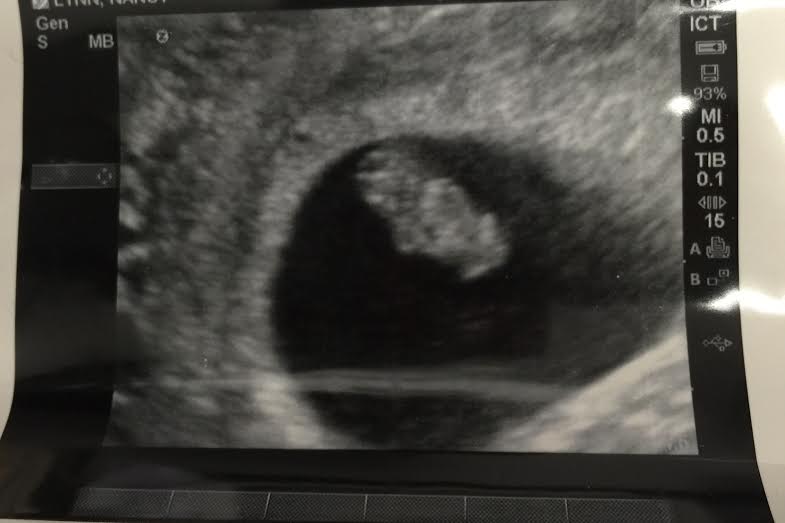

Here is my little one! We are 7 weeks 4 days baby was measuring 7 weeks 1 day and the heartbeat was 128bpm! Best thing ever to see that little heart flicker!